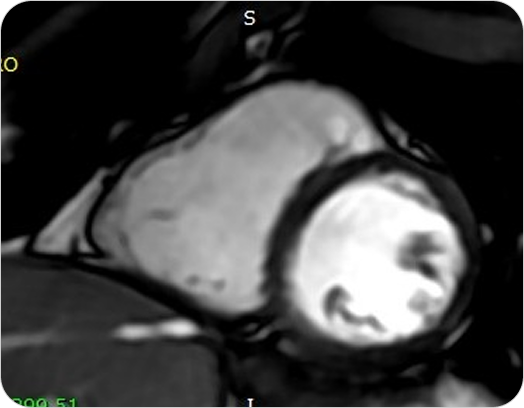

Resonancia Magnética Cardíaca

La resonancia magnética cardíaca es un estudio no invasivo y altamente especializado que permite obtener imágenes detalladas del corazón en movimiento. Brinda información precisa sobre la estructura, función, tejidos y vasos del corazón, sin utilizar radiación.

¿PARA QUE SE UTILIZA?

- Estudio de última generación para evaluar el corazón con altísima precisión, sin radiación. Diagnóstico completo de función, tejidos y circulación cardíaca.

- Evaluar la función del corazón y de las válvulas cardíacas.

Detectar infartos antiguos o recientes y analizar el daño al miocardio. - Diagnóstico de miocardiopatías (hipertrófica, dilatada, restrictiva, etc.).

- Detección de inflamación (miocarditis) o fibrosis del músculo cardíaco.

- Evaluación prequirúrgica o seguimiento de enfermedades cardíacas complejas.

- Estudio de tumores cardíacos o enfermedades congénitas.

¿POR QUÉ ES UN ESTUDIO DESTACADO?

- Estudio de última generación para evaluar el corazón con altísima precisión, sin radiación. Diagnóstico completo de función, tejidos y circulación cardíaca.

- Evaluar la función del corazón y de las válvulas cardíacas.

Detectar infartos antiguos o recientes y analizar el daño al miocardio. - Diagnóstico de miocardiopatías (hipertrófica, dilatada, restrictiva, etc.).

- Detección de inflamación (miocarditis) o fibrosis del músculo cardíaco.

- Evaluación prequirúrgica o seguimiento de enfermedades cardíacas complejas.

- Estudio de tumores cardíacos o enfermedades congénitas.

Resonancia Magnética Cardíaca

La resonancia magnética cardíaca es un estudio no invasivo y altamente especializado que permite obtener imágenes detalladas del corazón en movimiento. Brinda información precisa sobre la estructura, función, tejidos y vasos del corazón, sin utilizar radiación.

¿PARA QUE SE UTILIZA?

- Estudio de última generación para evaluar el corazón con altísima precisión, sin radiación. Diagnóstico completo de función, tejidos y circulación cardíaca.

- Evaluar la función del corazón y de las válvulas cardíacas.

Detectar infartos antiguos o recientes y analizar el daño al miocardio. - Diagnóstico de miocardiopatías (hipertrófica, dilatada, restrictiva, etc.).

- Detección de inflamación (miocarditis) o fibrosis del músculo cardíaco.

- Evaluación prequirúrgica o seguimiento de enfermedades cardíacas complejas.

- Estudio de tumores cardíacos o enfermedades congénitas.

¿POR QUÉ ES UN ESTUDIO DESTACADO?

- Estudio de última generación para evaluar el corazón con altísima precisión, sin radiación. Diagnóstico completo de función, tejidos y circulación cardíaca.

- Evaluar la función del corazón y de las válvulas cardíacas.

Detectar infartos antiguos o recientes y analizar el daño al miocardio. - Diagnóstico de miocardiopatías (hipertrófica, dilatada, restrictiva, etc.).

- Detección de inflamación (miocarditis) o fibrosis del músculo cardíaco.

- Evaluación prequirúrgica o seguimiento de enfermedades cardíacas complejas.

- Estudio de tumores cardíacos o enfermedades congénitas.